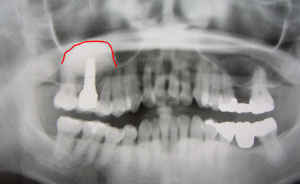

初診時のレントゲン

上顎洞底(→の部分)と言う骨と鼻の空洞の境界線が下に下りてきているため、インプラントを入れるには、骨の高さが不足しています。

それで、サイナスリフトと言う上顎洞底を押し上げる処置を行い、インプラントを入れることにしました。